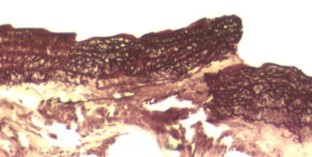

Former animal studies on laser-assisted microvascular anastomosis performed with CO2-, argon-, diode-, Holmium:YAG- and Nd:YAG-lasers had already proven the stability of the anastomotic sites. Tissue damage remained minimal along the anastomosis, while duration of the surgeries decreased significantly compared to that of traditionally implemented microvascular sutures. In addition to this, foreign body reaction next to end-to-end anastomosis appeared to be minimal due to fewer traditional stitches. This animal study was designed in order to investigate the durability and the histological properties of microvascular anastomosis assisted by KTP-532 laser. Twenty-one Wistar albino rats were used: in nine animals the KTP-laser-assisted microvascular anastomosis was carried out on the femoral artery. Those nine animals were divided into three groups and each of them consisted of three rats. The animals in these three groups were sacrificed 4 h, 1 and 4 weeks following the surgery, respectively. In three additional animals laser-assisted microvascular anastomosis was done on the abdominal aorta. Conventional microvascular sutures were carried out on femoral arteries of further nine animals in the control group. The healing process of the femoral arteries is documented with figures of histological slides both in the laser-treated and in the conventionally operated group of rats. The KTP-laser-assisted microvascular anastomosis failed on the abdominal aorta, as strong bleedings occurred after the traditional sutures had been taken out. However, the coagulative effect of the KTP-laser could still be used. The authors share the opinion that the success of the laser-assisted end-to-end microvascular anastomosis does not depend on the wavelength of the applied laser, but can be affected by both the calibre of the vessel and the intraluminal pressure.

Fig. 1

Fig. 2

Fig. 3

Fig. 4

Fig. 5

Fig. 6

Fig. 7

Fig. 8

Fig. 9